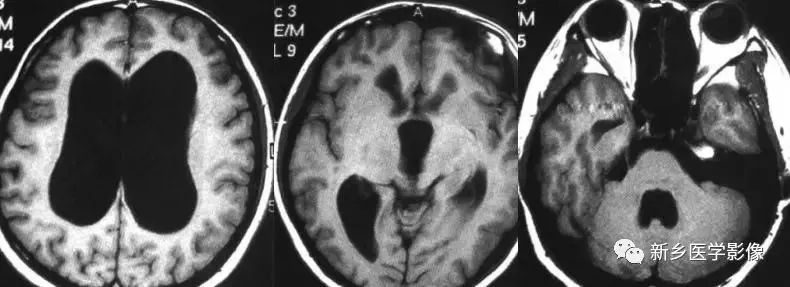

- Huntington s 病(亨廷顿舞蹈症):是一种常染色体显性遗传的、基底节和大脑皮层变性性疾病,主要损害基底节和大脑皮层,尾状核、壳核病变最明显。病理表现为:小神经节细胞严重破坏,大细胞也减少、尼氏体消失、核固缩、出现类淀粉小体,还有脱髓鞘改变和胶质增生,基底节部受累常最明显且发生最早。临床主要根据3大特征:舞蹈样动作、痴呆、家族史诊断。

无脑回和巨脑回

无脑回和巨脑回是一组因神经元移行异常所致的脑回发育异常。巨脑回也称平滑脑。巨脑回指有部分脑回存在,这些脑回异常增大增宽、脑沟变浅。巨脑回主要位于额、颞部。无脑回主要位于顶、枕部。

临床上,无脑回和巨脑回畸形患儿均表现有小头畸形和轻微的面部异常,完全无脑回畸形常在两岁前死亡。不完全无脑回畸形通常能长期存活。

CT和MR均能够很好显示无脑回和巨脑回畸形,表现为大脑半球表面几乎呈光滑状,仅可见少数宽阔、粗大、平坦的脑回,脑沟缺如。脑灰质增厚、脑白质变薄,灰白质分界面异常平滑,见不到白质向灰质内伸入的现象。常见透明中隔腔存在,侧脑室扩大,蛛网膜下腔增宽。